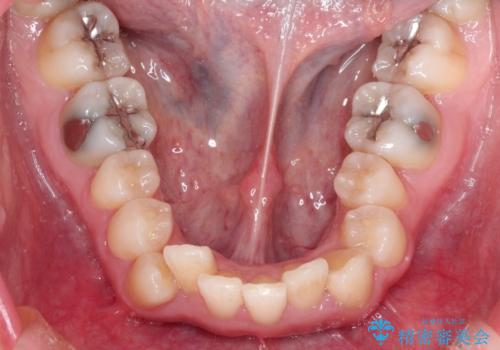

左上の犬歯が通常の位置より、かなり上方にあり、乳歯の残存と前歯のがたつきがありました。

残った乳歯と上下左右の永久歯を1本ずつ抜歯して、ワイヤーにて矯正することとしました。

犬歯も通常の位置にまで移動することができ、口元もすっきりすることができました。